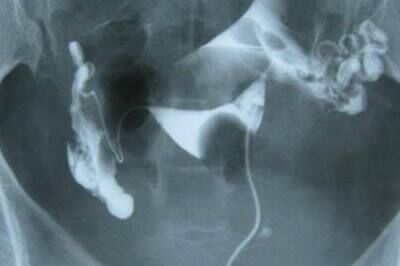

宫外孕保守治疗之后,输卵管处的包块需要一段时间才可以吸收,三个月之内最好不考虑怀孕,然后在三个月之后,需要进行输卵管的通液造影检查,确定下输卵管的通畅情况是否正常,以便正确处理,检查的时间最好选择是…

促排卵之前要不要做输卵管造影是要根据具体情况来决定的,不是必须的,但是也需要明确输卵管情况后才能进行促排卵治疗。如果有输卵管堵塞,促排卵是没有意义的。检查输卵管是否通畅的最好方法是输卵管造影。 …